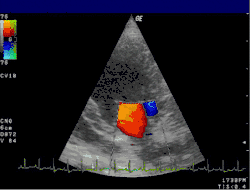

Doppler echocardiography is a procedure that uses Doppler ultrasonography to examine the heart.[1] An echocardiogram uses high frequency sound waves to create an image of the heart while the use of Doppler technology allows determination of the speed and direction of blood flow by utilizing the Doppler effect.

An echocardiogram can, within certain limits, produce accurate assessment of the direction of blood flow and the velocity of blood and cardiac tissue at any arbitrary point using the Doppler effect. One of the limitations is that the ultrasound beam should be as parallel to the blood flow as possible. Velocity measurements allow assessment of cardiac valve areas and function, any abnormal communications between the left and right side of the heart, any leaking of blood through the valves (valvular regurgitation), calculation of the cardiac output and calculation of E/A ratio[2] (a measure of diastolic dysfunction). Contrast-enhanced ultrasound-using gas-filled microbubble contrast media can be used to improve velocity or other flow-related medical measurements.